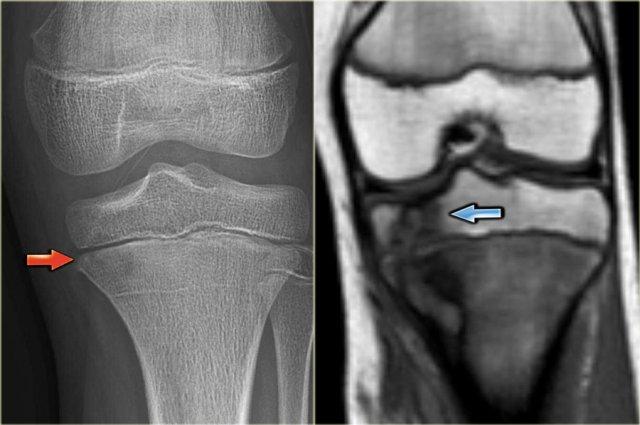

Chondromyxoid Fibroma

U xơ sụn nhầy là một tổn thương hiếm gặp.

U xơ sụn nhầy có hình ảnh tương tự u xơ không cốt hóa.

Vị trí ưu tiên: đầu gần xương chày và bàn chân.

Mặc dù tên gọi gợi ý rằng u xơ sụn nhầy là tổn thương sụn, nhưng thông thường không thấy hình ảnh vôi hóa.

Hình ảnh bên trái của một u xơ sụn dạng nhầy (CMF).

Có một tổn thương tiêu xương lệch tâm ở vùng hành xương của đầu gần xương chày.

Ở phía trong có một bờ xơ cứng.

Ở phía ngoài có sự phá hủy vỏ xương đều đặn với lớp xương ngoại vi.

Hình ảnh MRI cũng cho thấy bờ xơ cứng với cường độ tín hiệu thấp.

Discriminators :

- Mention when an NOF is mentioned.